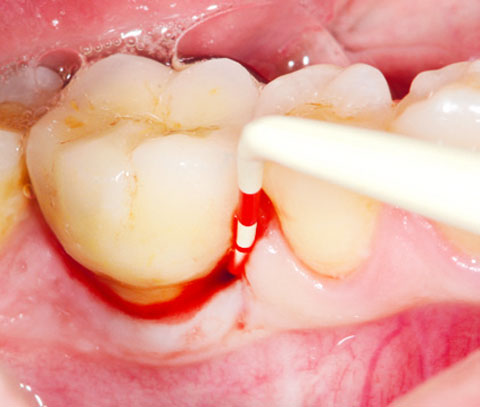

PERISOLV® für effektive nicht-chirurgische Instrumentierung

PERISOLV® kann bei folgenden Indikationen verwendet werden:

| Adjuvante nicht-chirurgische Behandlung tiefer Taschen in der initialen Aktiven Infektiösen Therapie (AIT) bzw. "Full Mouth Desinfection" (FMD) |

|

|

| Adjuvante nicht-chirurgische Behandlung tiefer persistierender Taschen in der Unterstützenden Parodontaltherapie (UPT) |

|

|

* Fördert bei der mechanischen Reinigung die Entfernung der Bakterien.